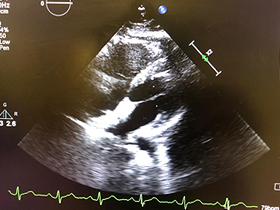

These diseases can be easily diagnosed with the help of a simple test known as echocardiography. This test is known as gold standard for diagnosis of heart defects.

Dr Gaurav Garg has a vast experience of performing more than 25000 echocardiography on babies of every age and weight with excellent results and efficacy. He performs every kind of echocardiography on children including 2 dimensional echocardiography, 3 dimensional echocardiography and transesophageal echocardiography.